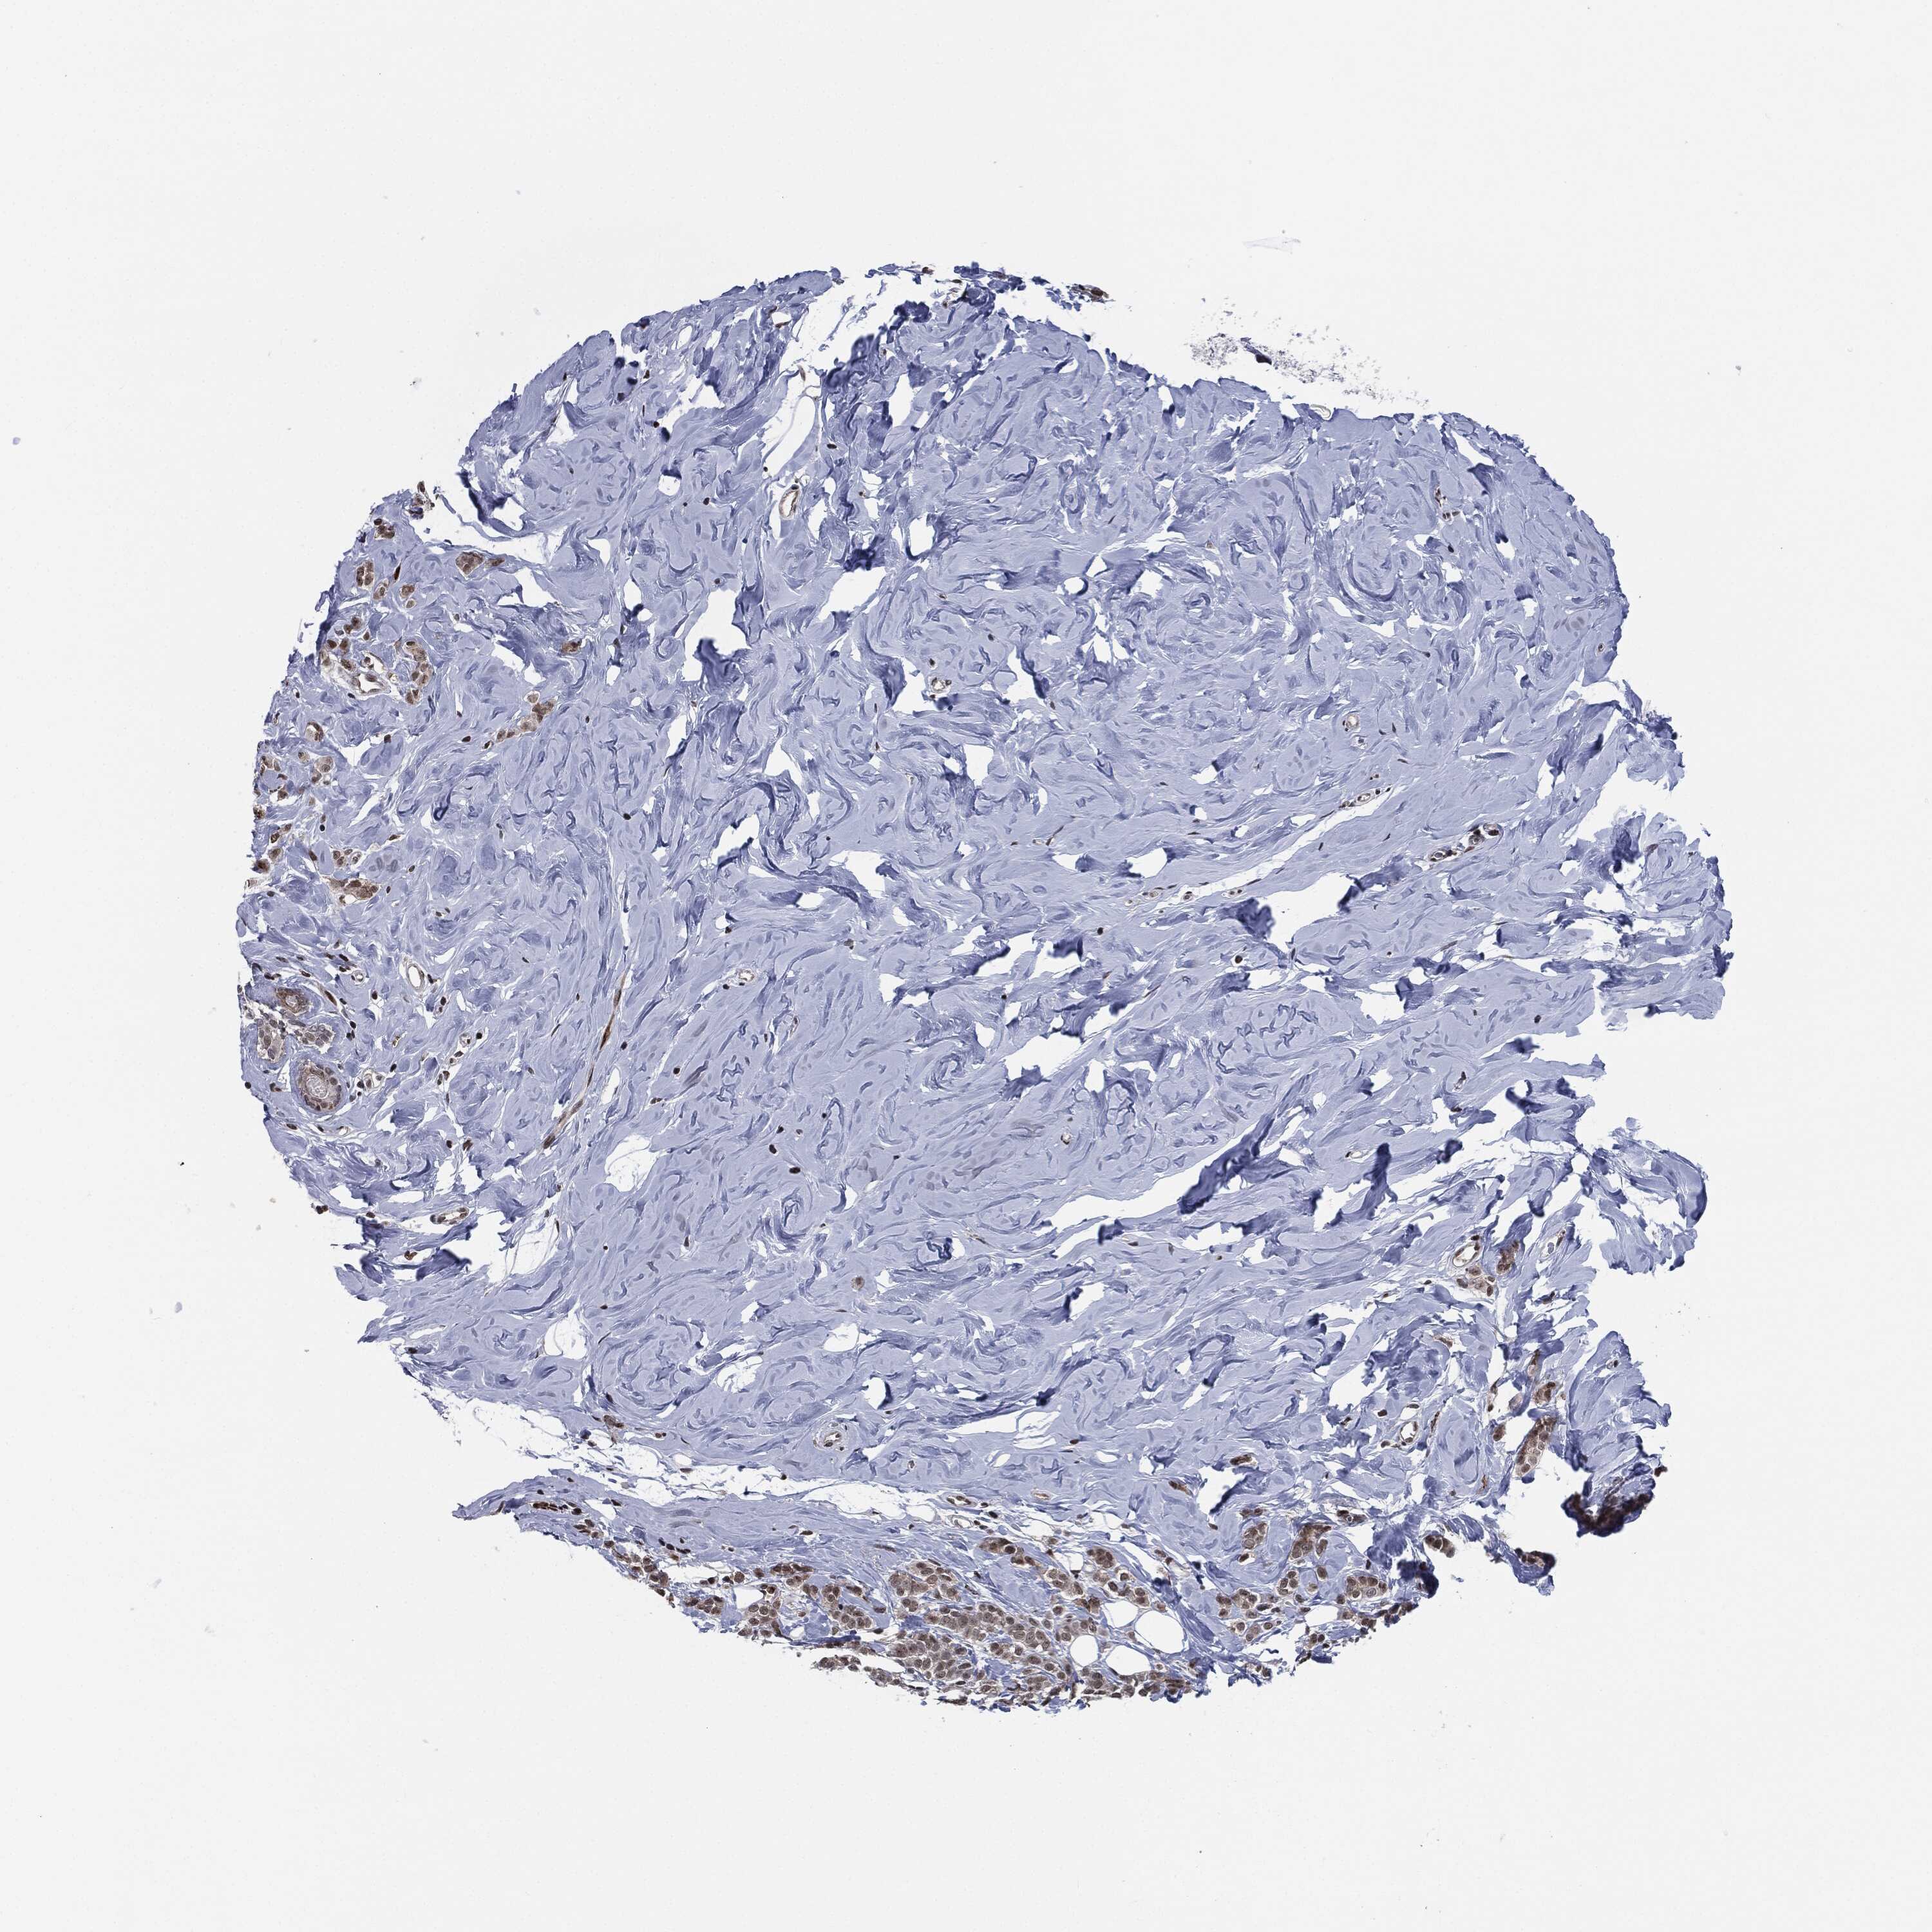

CANCER BREAST CANCER Show tissue menu

BRCA TCGA BRCA VALIDATION PROTEIN EXPRESSION